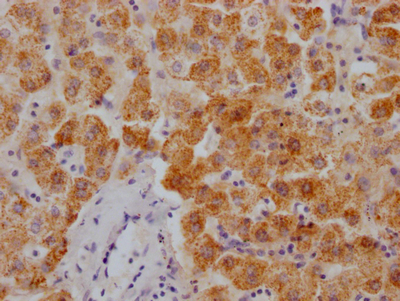

IHC image of CSB-RA169000A0HU diluted at 1:100 and staining in paraffin-embedded human liver cancer performed on a Leica BondTM system. After dewaxing and hydration, antigen retrieval was mediated by high pressure in a citrate buffer (pH 6.0). Section was blocked with 10% normal goat serum 30min at RT. Then primary antibody (1% BSA) was incubated at 4°C overnight. The primary is detected by a Goat anti-rabbit polymer IgG labeled by HRP and visualized using 0.05% DAB.